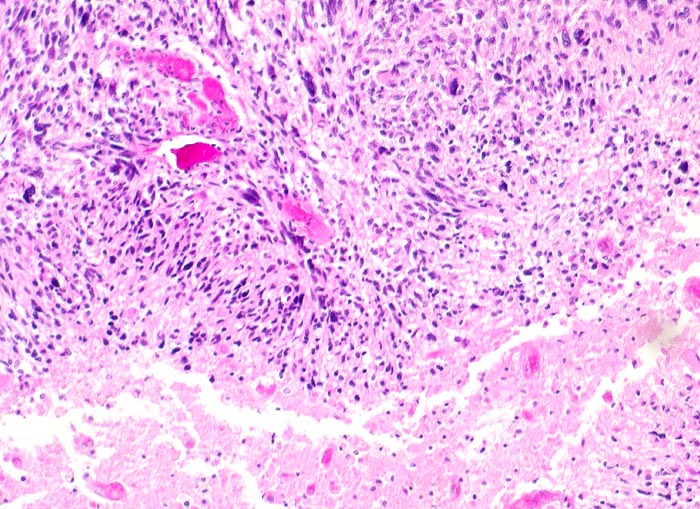

Glioblastoma multiforme WHO Grad IV

Das zytologische Bild gleicht einem hochmalignen Sarkom. Die Tumorzellen sind oft in mehreren Reihen um eine Kapillarachse herum angeordnet. Das Spektrum reicht von kleinen lymphozytenähnlichen Zellen bis zu grossen zytoplasmareichen und mehrkernigen Zellen. Das Kernchromatin ist grob retikulär und die Kerne sind embryonenartig gebuchtet. Mitosen sind oft anzutreffen. Das Zytoplasma kann degenerativ bedingte Vakuolen enthalten. Den Hintergrund bildet ein Gemisch aus fibrillärer Matrix, Blut, Detritus und Kalkpartikeln.